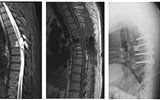

兰大二院骨科完成一例罕见的胸椎Cobb综合征的手术治疗